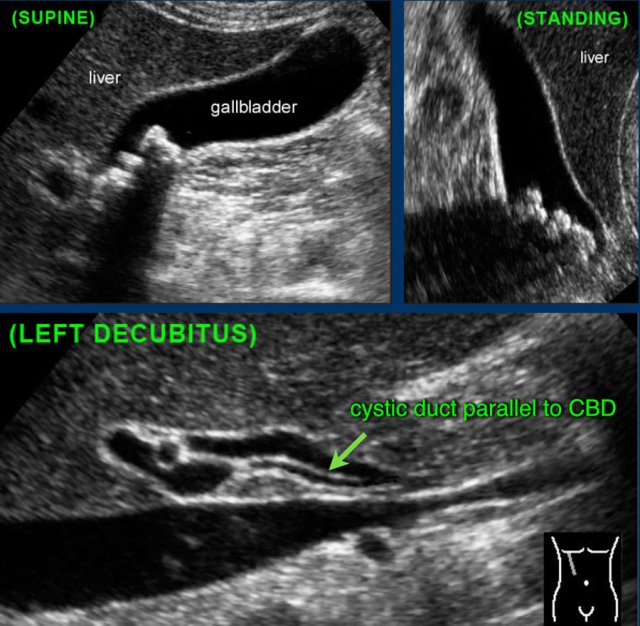

This patient had typical colic pain a few days before the examination.

In the standing position there are no obstructing stones in the gallbladder neck.

Even the cystic duct was seen with its typical course parallel to de common bile duct.